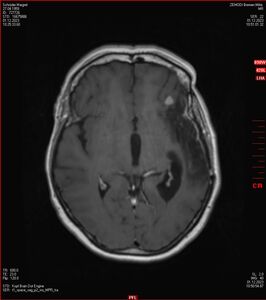

MRT vom 12. November 2024

So nun ein paar neue Bilder aus meinem Kopf. (Durch klicken bekommt man eine größe Ansicht eines Einzelbildes).

Die letzten drei Bilder Zeigen aus meiner Sicht den Tumor, der im Jahr 2021 bestrahlt wurde.

Ich denke, in den letzen 12 Monaten sind da ein paar Rezidive gewachsen,  vor 12 Monaten waren sie auch schon zu erkennen - vorher noch nicht. Nun hoffe ich auf den Rat des Spezialisten. Hoffendlich kann man etwas machen.